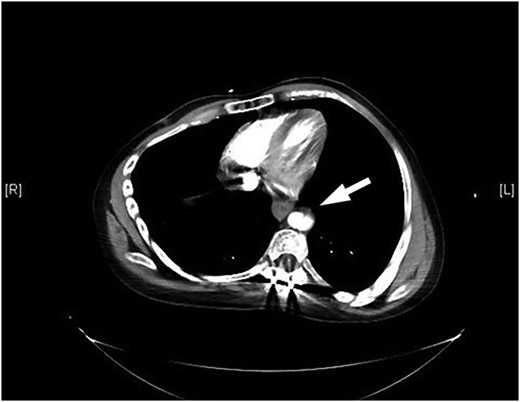

Our patient is a 24-year-old male with the EDS type VI who had undergone rod fixation of his spine for scoliosis, ocular surgery for a ruptured globe and ligation of his popliteal artery after an attempt was made to repair his aneurysm. The patient was being followed at Duke EDS Clinic where he underwent an extensive workup, and a definitive diagnosis was established. He presented to the emergency room (ER) after being kicked in the abdomen during a martial arts class. The patient felt an instant abdominal pain which resolved quickly. The patient went home after the incident and then developed nausea, vomiting and diaphoresis. He was hemodynamically normal in the ER. His groin pulses were slightly diminished compared with his radial pulses. The patient underwent a computed tomography (CT) scan of the chest, abdomen and pelvis with intravenous contrast. The patient was found to have traumatic aortic injury (Fig. 1). Cardiovascular surgery was consulted. The patient was admitted to the ICU for nonoperative therapy. He was started on Esmolol intravenously, and Diltiazem was added in order to keep his mean arterial pressure around 60. After 2 days in the ICU, the patient was transitioned to medications by mouth. He was allowed to ambulate on the fourth day and discharged on the eighth day after a long discussion with him and his family.